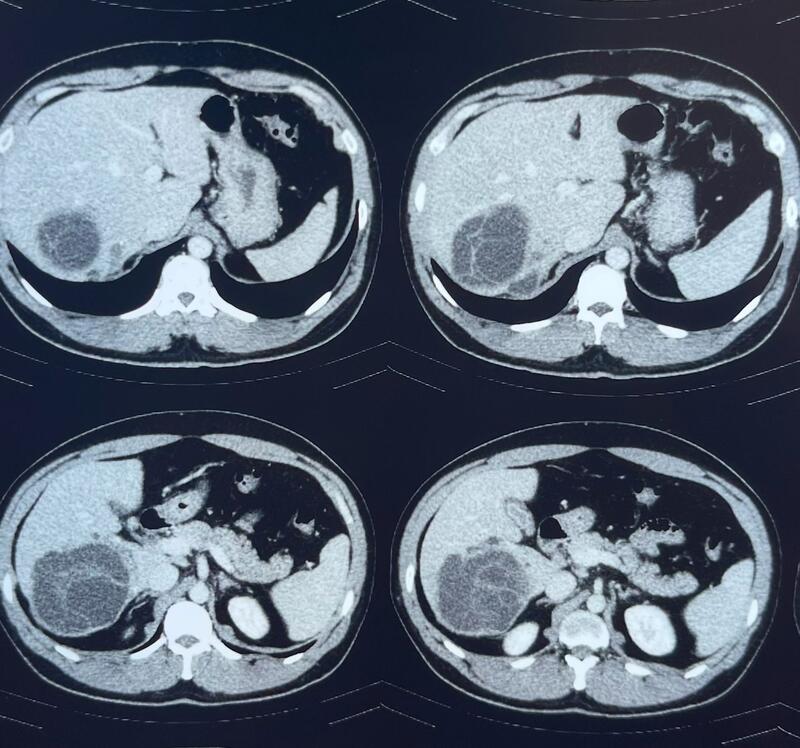

Case Capsule - Large Hydatid cyst liver with Obstructive jaundice